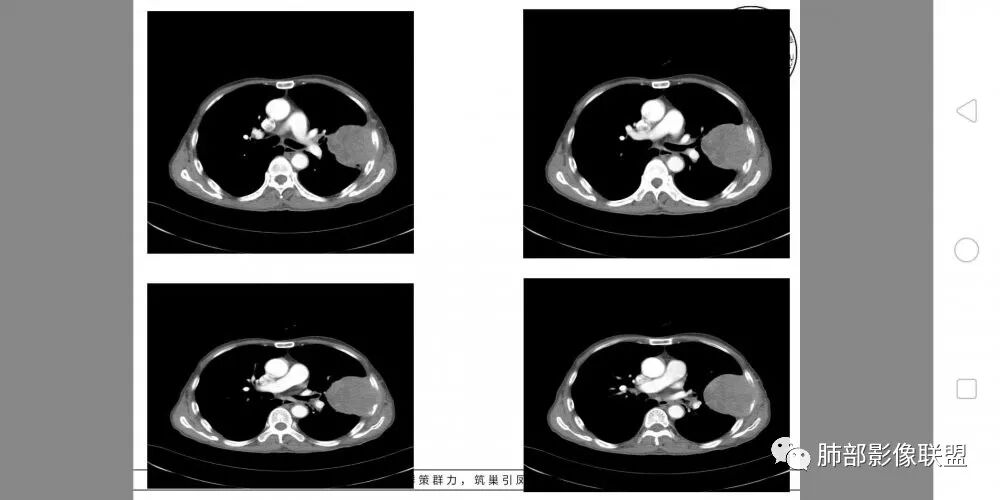

胸部CT所见左肺上叶尖后段胸膜下较大山丘形肿块,边界清楚,宽基底与胸膜相贴,边缘与胸膜呈直角及锐角相交。邻近上叶尖后段支气管受压推挤,叶裂局部膨隆,病灶周围见少许磨玻璃密度影,边界不清。纵膈窗显示,肿块密度均匀,增强扫描呈不均匀轻度强化,邻近肋骨骨质破坏,病变沿肋间隙向外侵犯,局部胸膜增厚。纵膈内见多发小淋巴结,未见胸腔积液征象。综合考虑恶性占位,肉瘤样癌可能性大。腰椎及髋部考虑骨转移。

病灶与叶裂之间夹有上叶下舌段支气管、血管。舌段支气管后移,尖后段支气管前移,病灶将支气管撑开。

叶裂受压后移,提示病灶不来源于叶裂。

支气管推移-----提示外朝内

近端肺动脉受压外移,但是有部分进入病灶内-------提示与肺有千丝万缕的关系。

不符合,因为病灶的主体在肺内,而且胸膜在病灶的外侧为主

与胸膜非钝角相交

病灶的整体形态--肺内边界清晰,膨胀性为主

如果是外面长进来的,胸膜掀起的角度一般更大,呈钝角

我们换个角度讲,如果是胸壁肋骨来源,病灶外朝内生长,并且朝内生长这么大,按理说应该是内侧侵袭性强,外侧侵袭弱。但是看这个病灶,外侧边界反而不清,内侧边界清,整个形态不太符合肋骨来源,而且胸膜局部增厚也不太符合胸壁来源。我认为肋骨来源应该以肋骨为中心,偏侧可以,但不会这么明显。而且血供也不一致,应该是肋间或胸壁动脉明显。

肋骨内侧面破坏为主,朝外有轻微的推移迹象。我觉得胸壁来源的放后面,特别是支气管的堵塞,这是肺外病变很少见的,SFT也有,罕见。

综合考虑恶性肿瘤,外朝内发展,倾向于肺内来源。